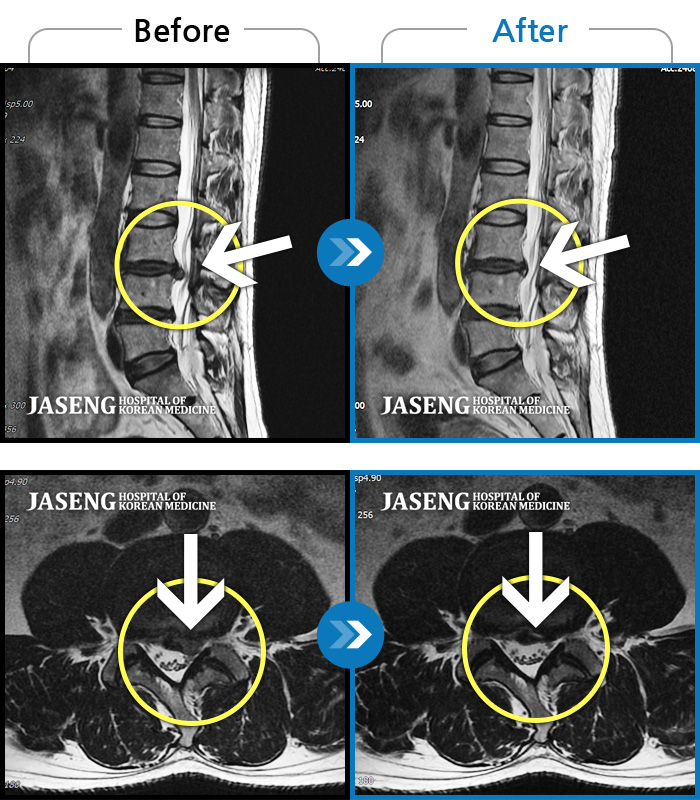

[뱸] 19.11.28~25.05.06

ȯںп Ǹ ǿ ԿǾ, ο ġ ۿ Ƿ ġḦ Ͻñ ٶϴ.